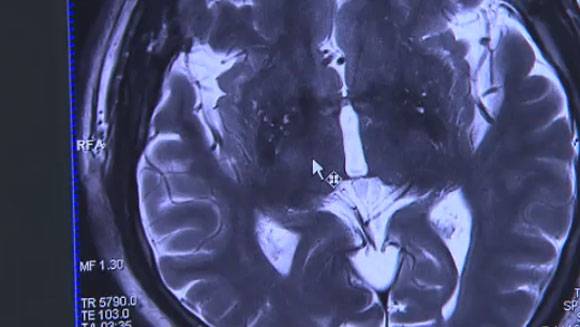

확률적으로 조영제 때문에 CT 촬영자 10만 명당 1명이 사망한다고 합니다. 그런데 그 1명이 나의 가족이거나 자신이면 너무나 억울하고 힘들 것 같습니다. 그렇다면 조영제가 뭐길래 병원에서 사용하고 부작용은 왜 생기는 걸까요? 사실 CT나 MRI 검사를 할 때 조영제 없이 그냥 찍을 수 있습니다. 두개골이나 얼굴, 갈비뼈의 미세골절 정도는 다 확인이 가능합니다. 그런데 뇌나 뱃속 장기들을 보거나, 복잡한 구조를 볼 때는 잘 구분이 가질 않습니다. 혈관조영제를 투입하면 일종의 인공물감 같아서 혈관이나 각종 장기는 물론, 숨은 암덩어리도 명확히 보이는 장점이 있습니다. 판독의 정확성이 높아지는 효과를 얻을 수 있는 겁니다. 그런데 아무래도 인공물질이다 보니, 부작용이 심심찮게 발생합니다. 식약처 자료에 보고된 이상반응 통계를 보면, 가장 흔한 부작용이 두드러기입니다. 다음으로 가려움증, 구토, 메스꺼움, 발진 순입니다. 모두가 가벼운 증상들입니다. 이게 다면 좋겠는데 문제는 치명적인 부작용도 있다는 겁니다. 심장정지나 신부전, 과민성 쇼크 등으로 사망하기까지 합니다.